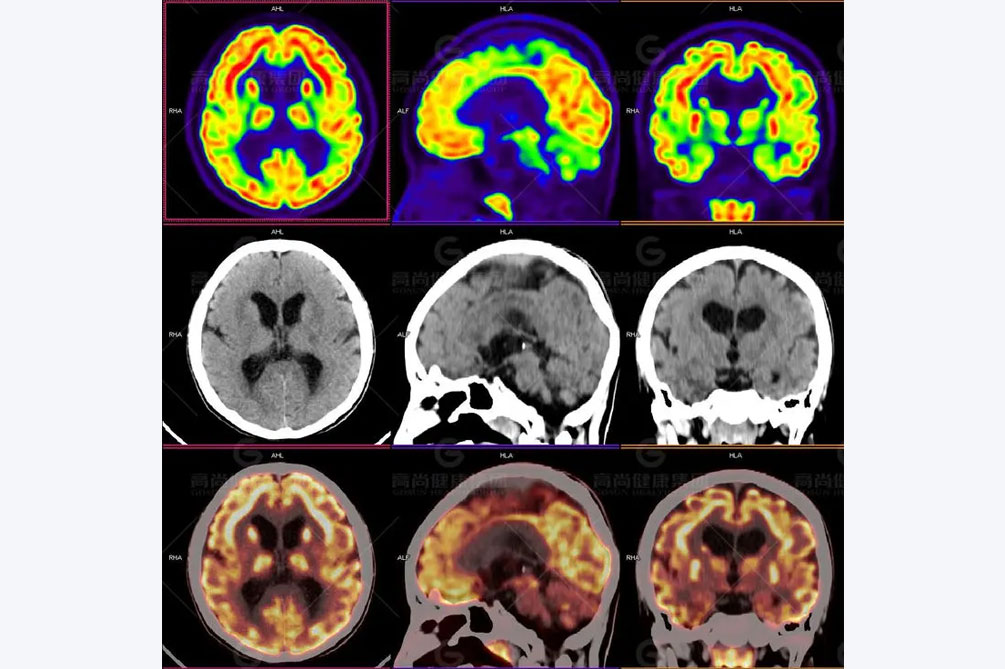

成人癫痫诊断需要做的检查,癫痫疾病是大脑神经元异常放电而导致,短暂的大脑功能障碍的一种慢性疾病,其中成年人是这种疾病的主要群体,更需要我们在生活中积极治疗,才能减轻此病对朋友生活的